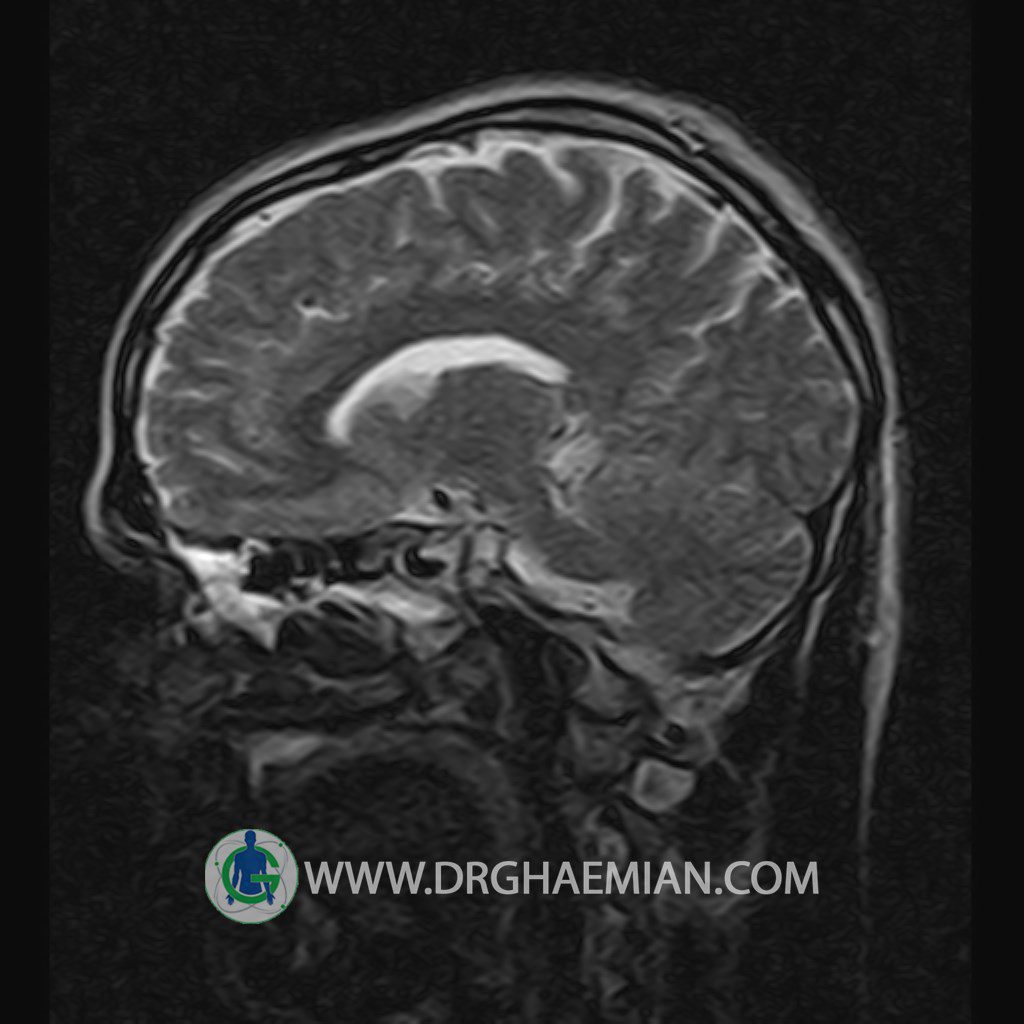

پزشکان اغلب از تصویربرداری ام آر آی برای تشخیص و درمان عارضه های پزشکی که فقط با استفاده از اشعه ایکس یا میدان مغناطیسی و امواج رادیویی قابل مشاهده است، استفاده می کنند. دستگاه ام آر آی تصاویر دقیق از ساختار های داخلی بدن ایجاد می کند. در این کیس یک میکروآدنوم در هیپوفیز بیمار مشاهده می شود.

HYPOPHYSIS MRI

(with and without contrast)

Technique: Axial , coronal T1 , Axial , coronal , sagittal T2 , Axial, coronal T1 post Gd & 64 dynamic thin coronal slices.

REPORT :

Imaging of the hypothalamus after contrast medium administration was normal.

– Small hypoenhancing mass lesion ( 3 x 4 mm ) in posterior of pituitary stalk suggestive for micro adenoma